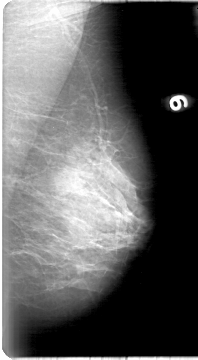

D_4018_1.RIGHT_CC

RIGHT_CC LINES 5251 PIXELS_PER_LINE 2611 BITS_PER_PIXEL 12 RESOLUTION 43.5 OVERLAY

FILE: D_4018_1.RIGHT_CC.OVERLAY

TOTAL_ABNORMALITIES 1

ABNORMALITY 1

LESION_TYPE MASS SHAPE ROUND MARGINS OBSCURED

ASSESSMENT 0

SUBTLETY 4

PATHOLOGY BENIGN

TOTAL_OUTLINES 1

BOUNDARY